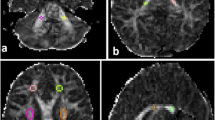

To study the MT phenomenon, a three-dimensional (3D) gradient echo sequence (TR/TE 32/8, flip angle 6°) was performed, and 4-mm/2-mm overlapping sections were concurrently obtained both with and without the application of MT binomial prepulse applied on-resonance. Images of this sequence obtained before application of MT prepulse had proton-density contrast due to the short TE and small flip angle (Fig. 1a). The MT sequence performed in the axial plane (perpendicular to the intercommisural line, i.e., the anterior commissure to posterior commissure line, or AC-PC line) was part of our standard protocol. Images obtained after application of the MT prepulse depict structures of high MTR with low signal intensity and those of low MTR with higher intensity (Fig. 1b). The duration of a complete MR examination ranged from 15 to 25 min. MTRs were calculated from circular regions of interest (ROIs), with a minimum size of 0.5 mm2. In all cases, UBOs observed on T2-weighted images were also detectable in proton density images of the MT sequence; therefore, ROIs were positioned at an image without MT and copy–pasted to the corresponding image with MT. Signal intensity measurements were performed bilaterally in the following regions: cortex and WM of the frontal and occipital lobe, caudate nucleus, putamen, globus pallidus, thalamus, optic chiasm, internal capsule, genu and splenium of the CC, hippocampus, cerebral peduncles, and cerebellar WM. Care was taken to avoid the partial volume effect of CSF when defining ROIs. MTR was calculated as: (SI0-SIm)/SI0×100% where SI0 is the signal intensity from the image acquired without a MT pre-pulse and SIm refers to signal intensity from an image acquired with MT prepulse.

UBOs in T2-weighted images lacking mass effect and enhancement after contrast infusion, compatible with “hamartomas,” were observed in the globus pallidus (6/7 patients), cerebral peduncles (3/7), periventricular WM (2/7), internal capsule (2/7), cerebellar WM (2/7), and hippocampus (1/7). Optic chiasm glioma appearing hyperintense in T2-weighted images and heterogeneously enhancing after contrast administration was observed in one patient. There was no significant difference in MTR values of normal-appearing GM and WM structures between patients and controls (Table 1). MTR of optic chiasm glioma (56.6) was lower compared with MTR of normal WM in controls (63.6±1.7). MTR values of UBOs in the different anatomic locations were significantly lower compared with MTRs of the corresponding normal-appearing anatomic regions in patients and controls (Table 1). The area of CC, WMV, GMV, and IBT were significantly larger in patients compared with controls (Table 2). There was no significant difference in CSFV between patients and controls (Table 2).